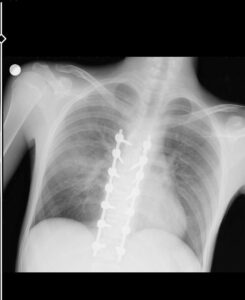

YUSUF GÜNDOĞMUŞ'UM VÜCUDUN TAKILAN PLATİNLER (BAHADIR TURGUT/ESKİŞEHİR-İHA)

"Beş gün entübe edildi. Ne olacağı belli değildi çıkmama ihtimali vardı. Şükürler olsun doktorlarımız ve Rabbim sayesinde entübeden çıktık. Hatta ciğerin birisinde infilak vardı; ciğer sorunumuzdan dolayı özellikle yoğun bakımda entübediydik. Beş günün sonunda ciğerleri toparlamaya başladı; entübeden çıkarttılar. Solunumu normale döndü. Sırayla sağlığı yerine gelmeye başladı. Bir hafta sonra kolundan ameliyat oldu platin koydular. Omurilikten ameliyat olduk. Omuriliğinde ilk röntgende tek kırık gördüler; üç kemiği birbirine bağlayacaklardı. Sonradan ikinci röntgende üç kırık olduğunu gördük; yedi kemiği birbirine bağladılar. Omuriliğe platin takıldı. 14 tane civatamız var. Şükürler olsun doktorlarımıza, Allah razı olsun. Evladımız gayet iyi, sağlıklı, yerinde. Artık işte suratta, çenede, burunda, elmacık kemiklerinde parçalı kırıklarımız var. Osman Gazi Fakültesi'nde Allah'ın izniyle buradaki hocalarımıza, önce Rabbim'e sonra hocalarımıza emanet çocuğumuz. İnşallah daha iyi olacağız; ben kendi adıma söylüyorum. Çocuğuma, her motora bindiklerinde sürekli kask ve montlarını giymelerini tembihliyordum. Giymediklerinde fırça atıyordum. Eskişehir'de birçok yerde tanınırız, tanırlar. Sevenimiz, eşimiz, dostumuz çok; uyarırlar, telefon gelir, haber verirler. Her duyduğumda, gördüğümde söylerim. Sağ olsun, çocuğum da o gün beni dinlemiş, kaskını takmış. Şükürler olsun ki takmış; takmasaydı o gün, o kazada belki çocuğumuzu kaybederdik